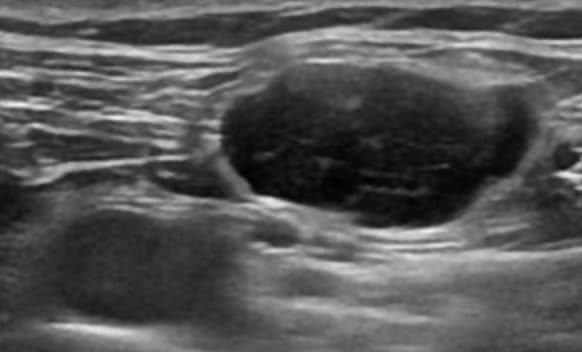

초음파 검사만으로는 악성 연조직종양을 진단할 수 없다. 그렇지만, 연조직 종괴가 인접한 관절과 분리되고, 내부의 괴사, 불규칙한 혈관 등을 가질 때 악성을 의심해 볼 수 있다. 연조직육종(soft tissue sarcoma)은 보통은 약간 낮은 에코를 보이나, 높은 에코, 과혈관성, 내부의 괴사에 의한 낮은 에코나 에코 없음을 보일 수 있다. 림프종(lymphoma)은 다양한 에코를 보이나, 주로 낮은 에코의 종괴로 나타나며, 메아리투과증가(through-transmission)에 의해서 깊은 부위가 밝게 보일 수 있다. 환자의 나이와 림프가 있을 위치에서 발견될 때 진단 가능하기도 하지만, 대부분은 경피적 조직검사가 필요하다.

림프종 초음파 영상 초음파유도하생검을 하면 인접한 혈관과 종괴 안의 괴사 부위를 피해서 바늘의 끝을 정확하게 종괴의 고형 부분에 위치시킬 수 있으므로 진단정확도를 높일 수 있다. 악성질환의 연조직 전이는 과혈관성의 다양한 에코의 종괴로 보인다. 초음파검사는 연조직 악성질환 치료 후 경과 관찰에서 연조직에 재발한 종괴를 찾는데도 이용된다.